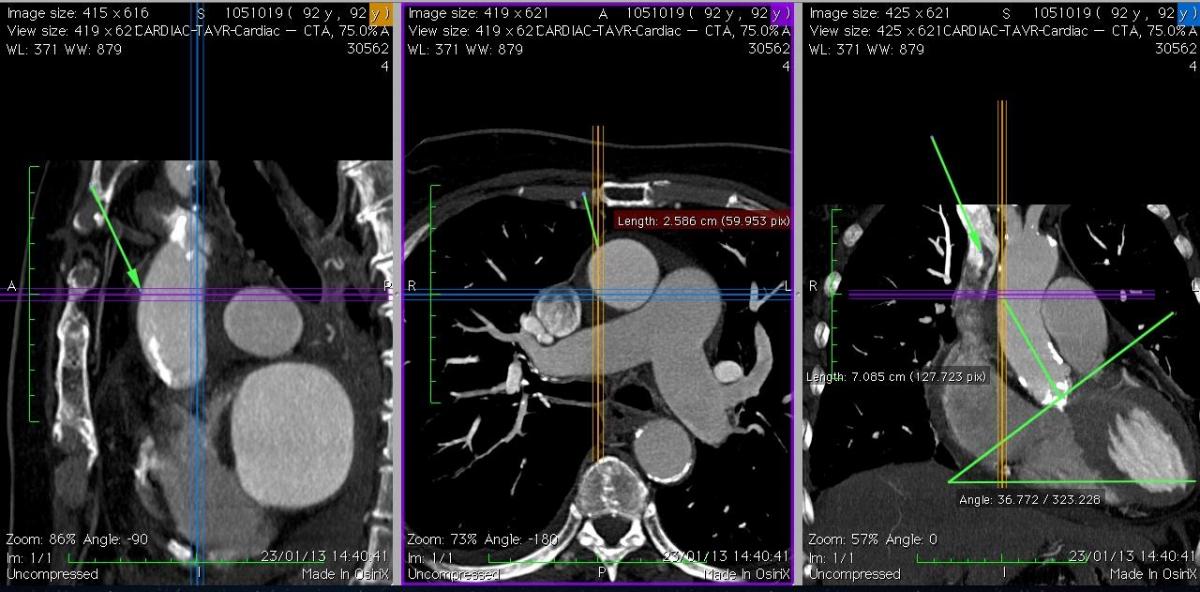

- In the case of minithoracotomy, the rib above the incision may be cut at the cartilage, then reapproximated. - If the axial CT views demonstrate the aorta is central, behind the sternum, or left-sided, an upper ministernotomy is recommended. If the axial CT views demonstrate that the aorta is on the right of the sternum and/or horizontal (angle >40-45°), a minithoracotomy is suggested, unless other specific anatomical or clinical contraindications exist.

- These images provide information regarding the angle of the aortic annulus plane with respect to the horizontal plane. If the horizontal aorta angle is >40-45°, a minithoracotomy usually provides the ideal coaxial access.

- If the aorta is vertical, a ministernotomy is better. The aortic annulus angle plane can be measured in the coronal CT views. The coronal views are also used to measure the distance between the aortic annulus and the proposed aortic puncture site.

- If the horizontal aorta angle is >75°, a trans-apical approach may be preferred.

Fig. 5A: Case 1. The coronal view (right picture) shows a “vertical” aorta, and the ideal coaxial direction of the delivery system, with a suitable puncture site at 7 cm. The axial view (middle) shows that the ascending aorta is central (behind the sternum) and free of calcification at the level of the projected puncture site.

Fig. 6A: Case 2. In comparison to Case 1, the ascending aorta is more horizontal, and right-sided relative to the sternum. It was possible in this case to find a suitable puncture site at about 8 cm from the aortic annulus.